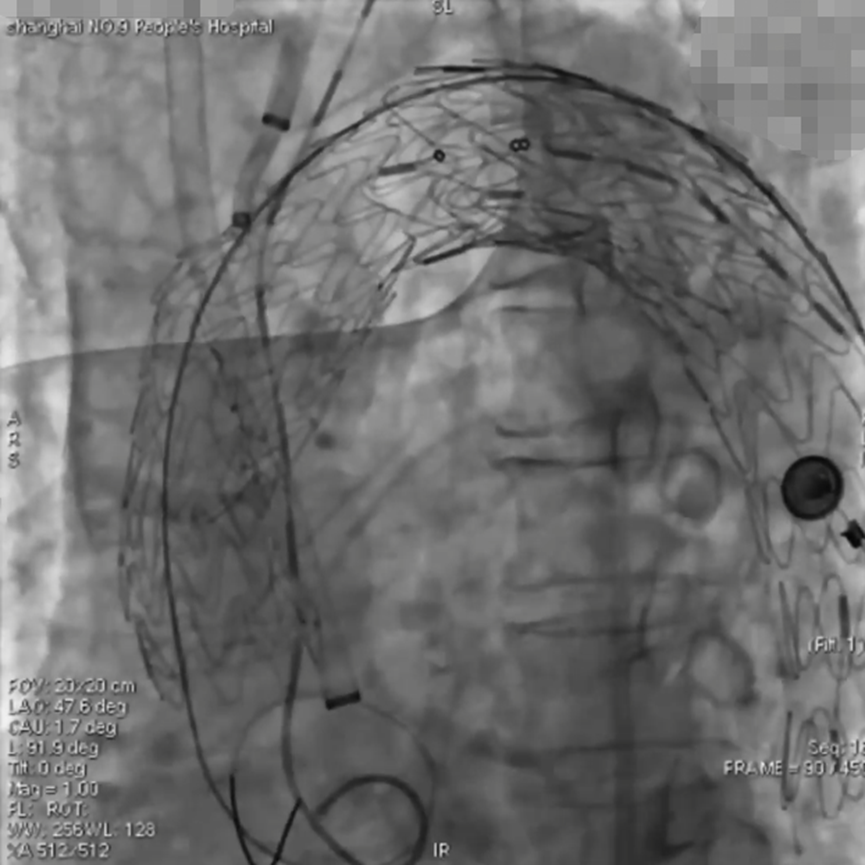

手术过程(一):术中造影证实为A型主动脉夹层,破口靠近升主动脉累及弓上分支动脉。行颈动脉转流,保持脑灌注。远端植入先健覆膜支架。

波科支架怎么样陆信武:激光原位开窗重建弓上分支治疗A型主动脉夹层_https://www.jmylbn.com_新闻资讯_第4张

手术过程(二):升主动脉植入戈尔覆膜支架,近端定位于冠脉以远1 cm,其近心端与头臂干导管鞘齐平。